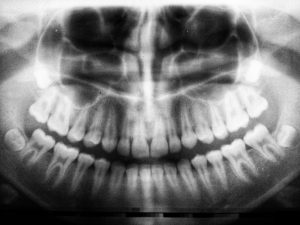

Røntgenundersøgelse

image